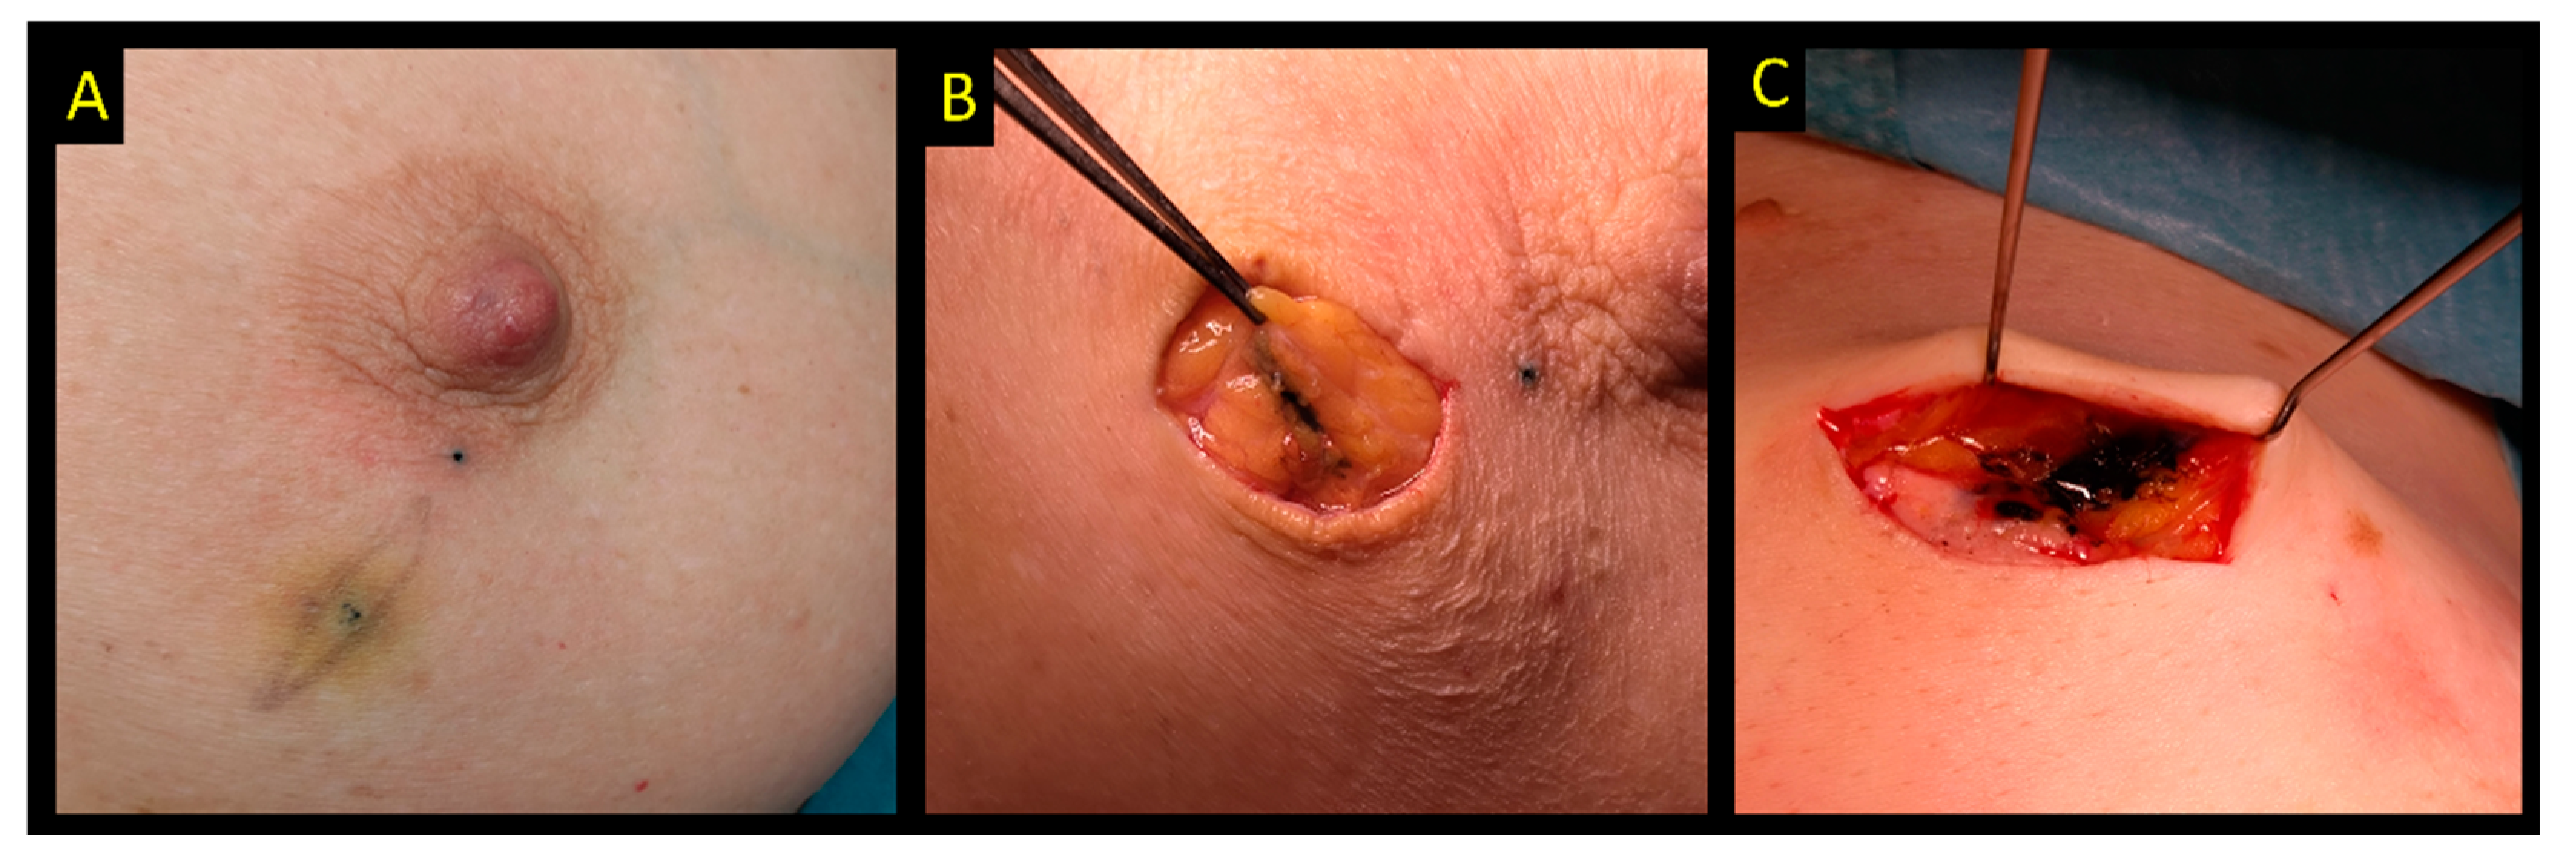

2.8. Carbon Suspension

- Canavese, G.; Catturich, A.; Vecchio, C.; Tomei, D.; Estienne, M.; Moresco, L.; Imperiale, A.; Parodi, G.C.; Massa, T.; Badellino, F. Pre-operative localization of non-palpable lesions in breast cancer by charcoal suspension. Eur. J. Surg. Oncol. 1995, 21, 47–49. [Google Scholar] [CrossRef]

- Ko, K.; Han, B.K.; Jang, K.M.; Choe, Y.H.; Shin, J.H.; Yang, J.H.; Nam, S.J. The value of ultrasound-guided tattooing localization of nonpalpable breast lesions. Korean J. Radiol. 2007, 8, 295–301. [Google Scholar] [CrossRef]

- Mathieu, M.C.; Bonhomme-Faivre, L.; Rouzier, R.; Seiller, M.; Barreau-Pouhaer, L.; Travagli, J.P. Tattooing breast cancers treated with neoadjuvant chemotherapy. Ann. Surg. Oncol. 2007, 14, 2233–2238. [Google Scholar] [CrossRef]

- Porpiglia, M.; Borella, F.; Chieppa, P.; Brino, C.; Ala, A.; Marra, V.; Castellano, I.; Benedetto, C. Carbon tattooing of axillary lymph nodes in breast cancer patients before neoadjuvant chemotherapy: A retrospective analysis. Tumori 2022. [Google Scholar] [CrossRef] [PubMed]